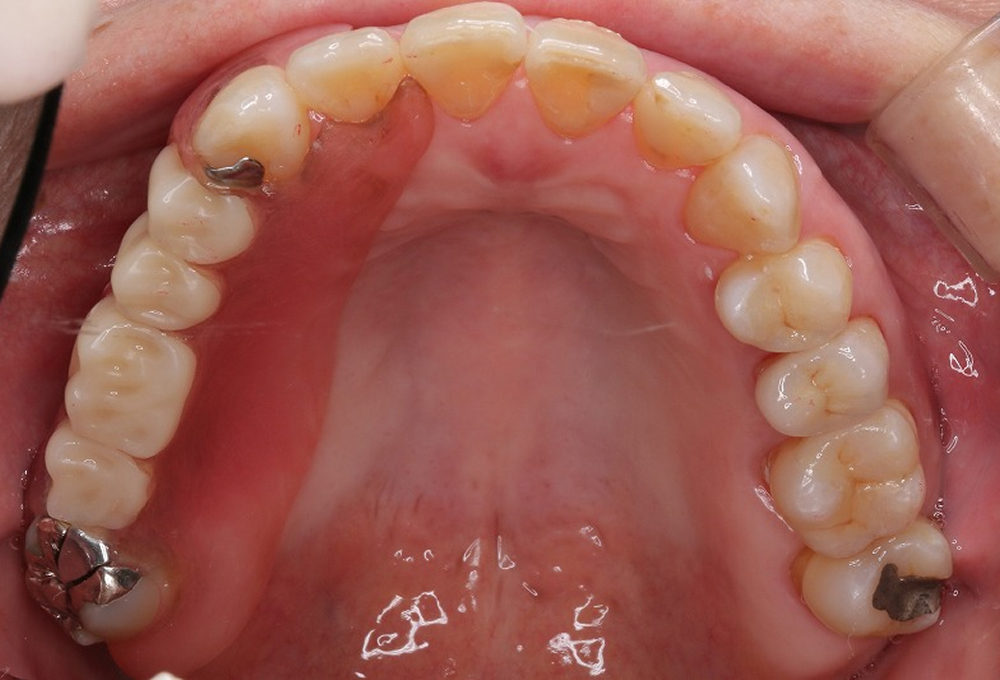

②術前上顎